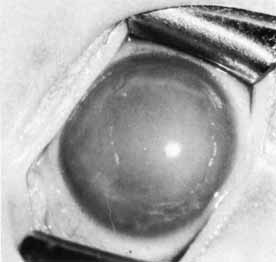

Corneal clouding and breaks in Descemet's membrane are also important in the evaluation of congenital glaucoma (Fig. 10). When corneal clouding is marked, it may be necessary to remove edematous corneal epithelium to view the other ocular structures. Developmental anomalies of the cornea and iris must be noted because they may alter diagnosis and treatment. Gonioscopy is performed by use of a gonioprism or a Koeppe lens with a Barkan light and binocular microscope. The Koeppe lens also aids in viewing the lens, vitreous, and fundus. It neutralizes irregular corneal surfaces and improves the view of the optic nerve through a small pupil, allowing the entire optic nerve head to be seen within one field. Optic nerve evaluation is the most important part of the glaucoma evaluation. Glaucomatous disc changes occur more rapidly in infants and at lower pressures than in older children or adults. Cup-to-disc ratios greater than 0.3 are rare in normal infants and must be considered highly suspicious of glaucoma (Table 3).14

with other ocular or systemic diseases. Seventy-five percent

cases present before 1 year of age. Sporadic occurrence is observed in approximately 90% of cases. The remainder demonstrate an autosomal recessive pattern with variable penetrance or a polygenic inheritance pattern.17,18 Siblings of an affected child should be examined for glaucoma. Advances have recently been made in the identification of genetic mutations associated with congenital glaucoma, including two chromosomal localizations on 2p21 (GLC3A) and 1p36 (GLC3B).19–22 For some CLC3A-linked families, various mutations in the cytochrome P4501B1 (CYP1B1) gene are found.23,24 One theory is that CYP1B1 is involved in the metabolism of a molecule important for the normal development and function of the anterior segment.19 Primary congenital glaucoma presents clinically with epiphora, photophobia, and blepharospasm. Examination often reveals increased corneal diameter, corneal cloudiness (Fig. 12), and breaks in Descemet's membrane. Other findings include an intraocular pressure greater than 21 mm Hg, isolated trabeculodysgenesis on gonioscopy, and increased optic nerve cupping.